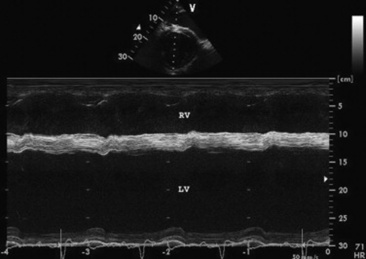

Most animals with valvular heart disease have no clinical signs but have a cardiac murmur that is detected during a routine examination. The clinical signs vary depending on the severity of the lesion and its rate of development. Murmurs of valvular heart disease are frequently holosystolic (Fig. 30-6), pansystolic, or holodiastolic (Fig. 30-7). They radiate from the PMI in the direction of the abnormal blood flow; are coarse and band-shaped, crescendo or honking (if systolic), or decrescendo and blowing or musical (if diastolic); and are usually moderate to loud in intensity (≥grade 3/6) but may be softer if holodiastolic. All of these characteristics help distinguish these murmurs from functional or innocent murmurs, which generally occur early or late in systole or diastole but can be holosystolic; are soft and blowing or crescendo-decrescendo in quality; are localized to a small area; do not radiate; and are soft to moderate in intensity (≤3/6). The intensity of the murmur is not a reliable indicator of the severity of the lesion, except in horses with tricuspid regurgitation, in which the longer, louder murmurs are associated with a larger jet of tricuspid regurgitation.80 In cattle, in particular, severely involved valves (usually in cattle with endocarditis) commonly have faint or no audible murmurs.

image

Fig. 30-6 Phonocardiogram obtained from a horse with a ruptured mitral valve chorda tendineae. A loud, plateau-shaped holosystolic murmur (SM), which is variable in intensity, occurs when the free wall leaflet of the mitral valve is prolapsing into the left atrium.

Fig. 30-7 Phonocardiogram and M-mode echocardiogram obtained from a horse with a holodiastolic murmur (DM) caused by aortic valve regurgitation. The M-mode echocardiogram shows diastolic flutter (arrows) of the septal mitral valve leaflet, characteristic of aortic valve insufficiency.